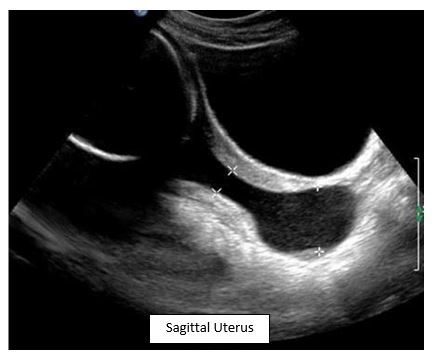

Question 3: What is most commonly associated with this finding during a second trimester ultrasound?

This is an example of cervical funneling in cervical incompetence. Most cases are idiopathic, but known causes include previous preterm delivery, previous cervical procedures and DES exposure.

A. Oligohydramnios is associated with cervical incompetence from premature rupture of membranes.

B. and C. This is not associated with cervical incompetence.